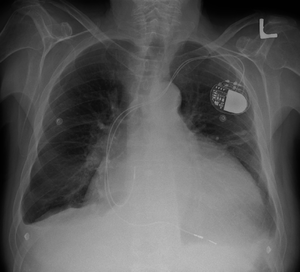

Cardiomegaly on chest X-ray and a pacemaker

1. Chest X-Ray: X-ray images help see the condition of the lungs and heart. If the heart is enlarged on an X-ray, other tests will usually be needed to find the cause.

Pacemaker: Coordinates the contractions between the left and right ventricle. In people who may be at risk of serious arrhythmias, drug therapy or an implantable cardioverter-defibrillator (ICD) may be an used.